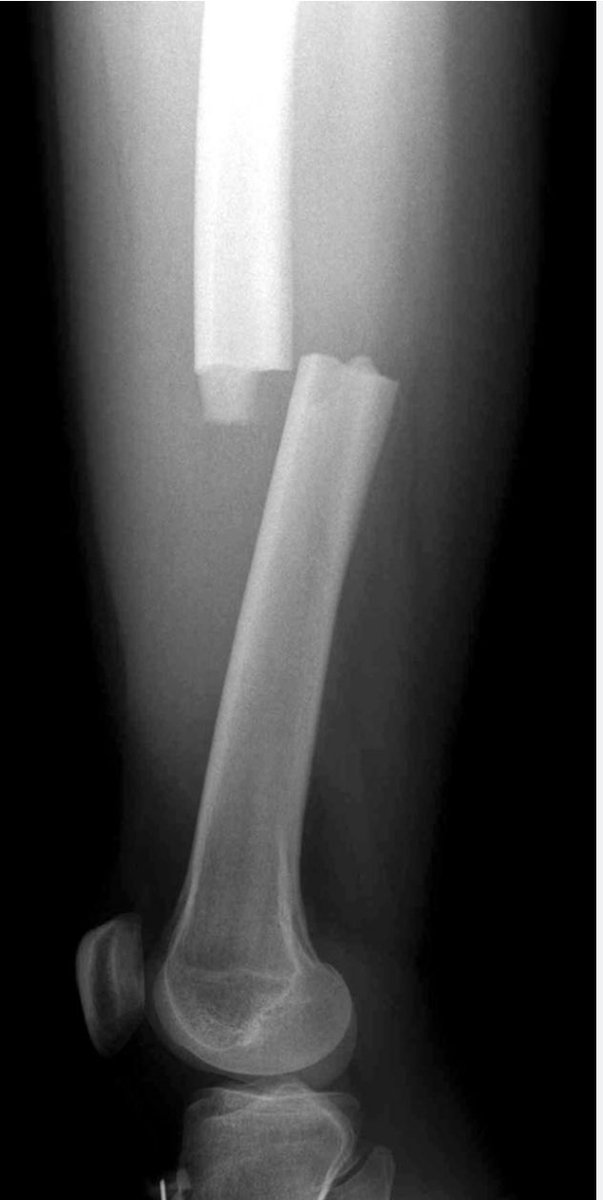

Перелом Бедра Фото Рентген

Перелом Бедра Фото Рентген 138 фото